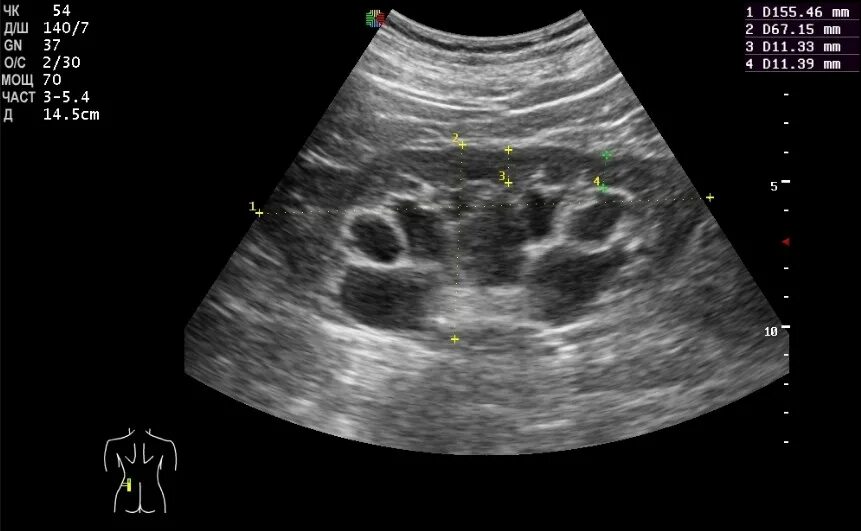

Медуллярная кистозная дисплазия почек узи. гиперэхогенные пирамиды на узи. гиперэхогенные пирамиды в почках на узи. кортико-медуллярная дифференциация выражена узи почек.

Гиперэхогенные пирамидки в почках на узи. синдром гиперэхогенных пирамидок почек. синдром гиперэхогенных пирамид почек узи. медуллярная кистозная дисплазия почек узи.

Синдром гиперэхогенных пирамид на узи. синдром гиперэхогенных пирамид почек узи. расширение пирамидок в почках на узи. гиперэхогенные пирамидки в почках на узи.